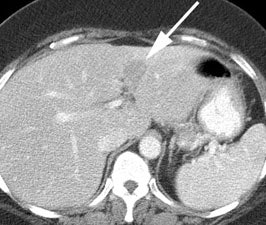

Monitoring response to radiofrequency ablation: The patient below had a remote history of radiofrequency ablation for metastatic colon cancer. The right lobe liver lesion was stable on CT scan (white arrow), but the patients CEA level was increasing. A PET scan confirmed a focus of recurrent tumor at the margin of the prior lesion. |